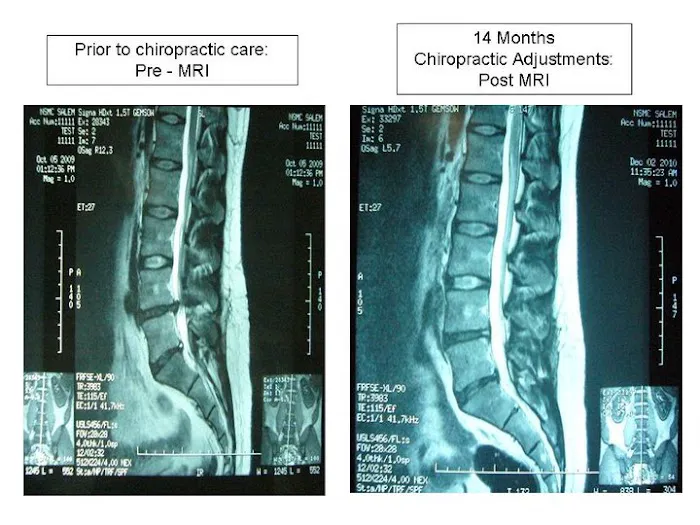

Chiropractic care is a widely recognized healthcare profession focused on the diagnosis, treatment, and prevention of disorders of the musculoskeletal system, with a primary emphasis on the spine. The foundational principle of chiropractic is that proper alignment and function of the spine are crucial for the body's nervous system to operate optimally, thereby facilitating the body's innate healing capabilities without the need for medication or surgery. Chiropractors, like Dr. Wright at Sports & Family Chiropractic, are highly skilled in utilizing precise manual adjustments and other therapeutic techniques to restore proper joint movement, reduce nerve interference, and alleviate pain. Beyond addressing common conditions such as back pain, neck pain, headaches, and sciatica, many chiropractors also specialize in areas like sports injury rehabilitation and family wellness, catering to patients of all ages, from newborns to seniors. Their holistic approach often extends to offering guidance on exercise, nutrition, and lifestyle modifications, empowering patients to take an active role in their long-term health journey.

Spinal Adjustments and Manipulations: The cornerstone of chiropractic care, involving precise techniques to correct spinal misalignments, reduce nerve interference, alleviate pain, and improve overall body function and mobility.

- Disc Condition Treatment

- Herniated Disc Treatment

- Bulging Disc Treatment